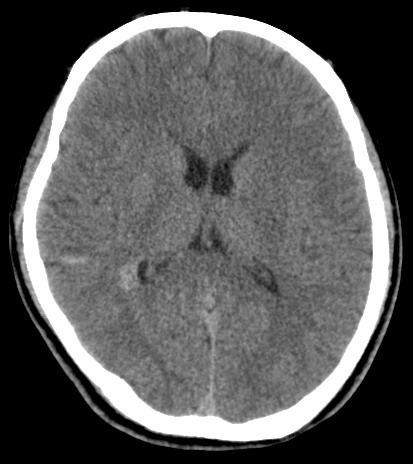

男,31岁,头疼就诊,其他不祥。

考虑右颞叶脑血管畸形伴出血。avm可能大,建议dsa。

平扫见右颞叶、右侧脑室后角旁略高密度影,增强未见明显病灶,基本正常。不放心做mri检查

病灶呈略高密度,周围伴环形水肿,无强化/无异常av影........

考虑为:1.脑内小血肿?   2.脑灰质异位?   建议mri检查........

考虑右颞叶脑血管畸形伴出血。考虑静脉血管瘤,深部型的,avm不除外,建议dsa。